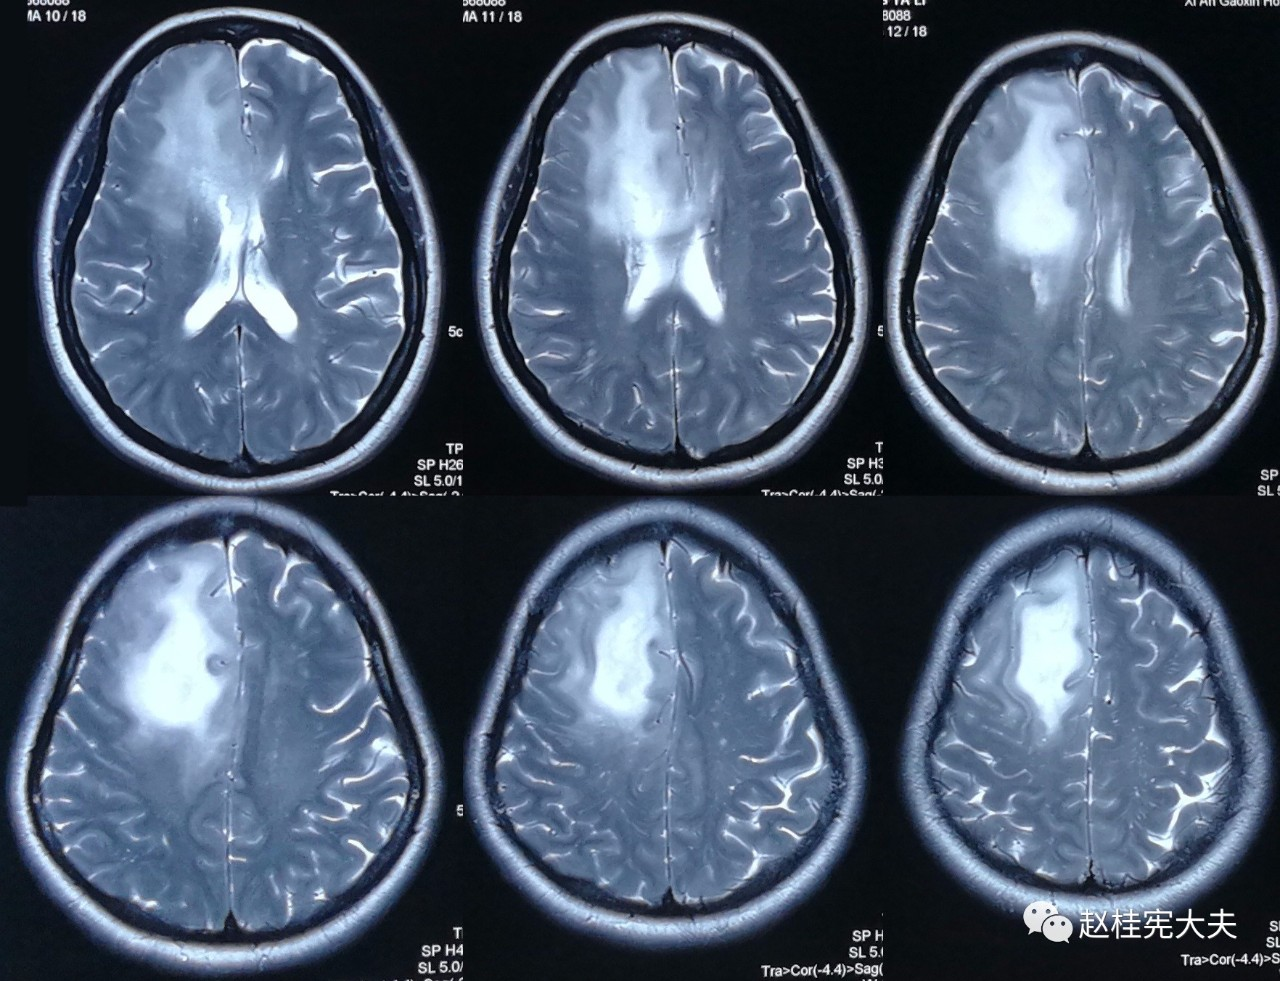

为了更直观,我们先看看其中1例患者的脑白质病变影像学的改变吧:

2017.10

可以看到,随着时间的延长,脑白质的T2异常信号范围不断扩大,并且出现了脑室扩大,脑萎缩。